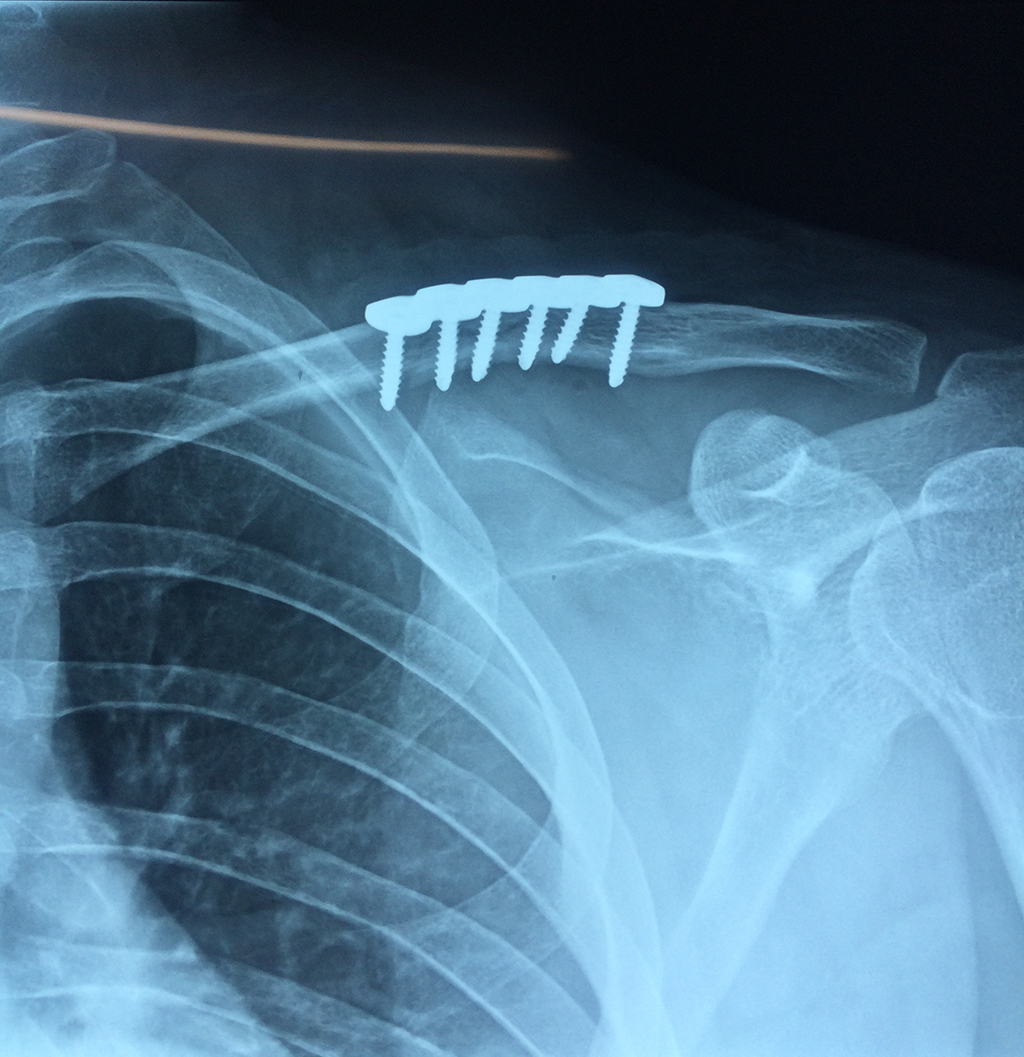

Cirugias en El Salvador - Clavícula